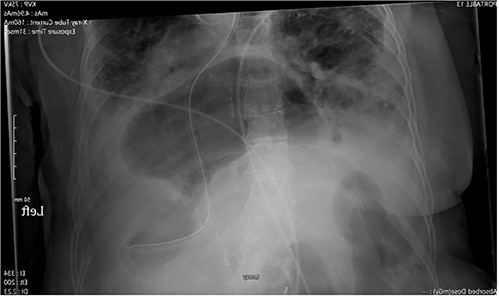

Abdominal radiography demonstrated a large hiatal hernia with intrathoracic stomach and concerns for gastric volvulus and partially imaged bowel gas within the right upper abdomen (Fig. 1). Computerized tomography of the chest and abdomen showed a large distended hiatal hernia with organoaxial rotation of the stomach, gastric distention with fluid and gas raising concern for partial obstruction. The right hemithorax contained multiple mildly dilated fluid-filled loops of small bowel with a prominent infiltrate of mesentery and decompressed bowel distally concerning for strangulation by a posterior lateral diaphragmatic hernia. There was no evidence of pneumatosis (Fig. 2).

X-ray of the abdomen: anterior–posterior portable X-ray of the abdomen showing bowel gas pattern in the right upper abdomen and a large hiatal hernia with gaseous distention of the stomach.